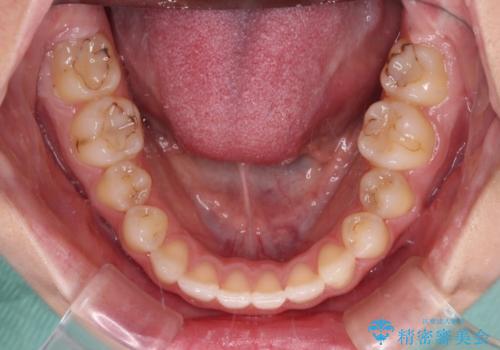

治療期間の目安は2年半~3年間でしたが、予定通り治療が進み、2年半弱で終えることができました。

歯列はきれいに整い、治療期間も予定通りであり、患者様には大変満足していただきました。